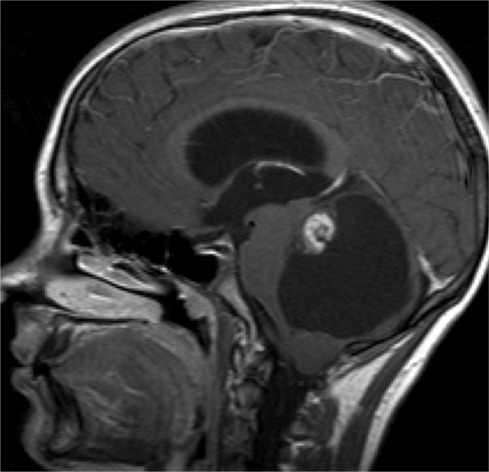

Amigdalar

- Por descenso de las amígdalas por el agujero magno.

- Lo normal es que las amígdalas cerebelosas (en imágenes sagitales)estén 5 mm por debajo del agujero magno en adultos y 7 mm en niños.